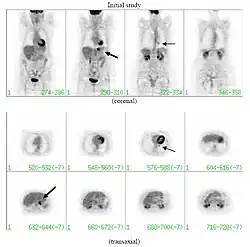

If there is an intermediate risk of malignancy, further imaging with positron emission tomography (PET scan) is appropriate (if available). It can be done simultaneously as a CT scan in the form of PET-CT. Around 95% of patients with a malignant nodule will have an abnormal PET scan, while around 78% of patients with a benign nodule will look normal on PET (this is the test sensitivity and specificity).[15] Thus, an abnormal PET scan will reliably pick up cancer, but several other types of nodules (inflammatory or infectious, for example) will also show up on a PET scan. If the nodule has a diameter of less than one centimeter, PET scans are often avoided because of an increased risk of falsely normal results.[15][16][17] Cancerous lesions usually have a high metabolism on PET, as demonstrated by their high uptake of FDG (a radioactive sugar).

-

PET-CT of a tuberculoma.